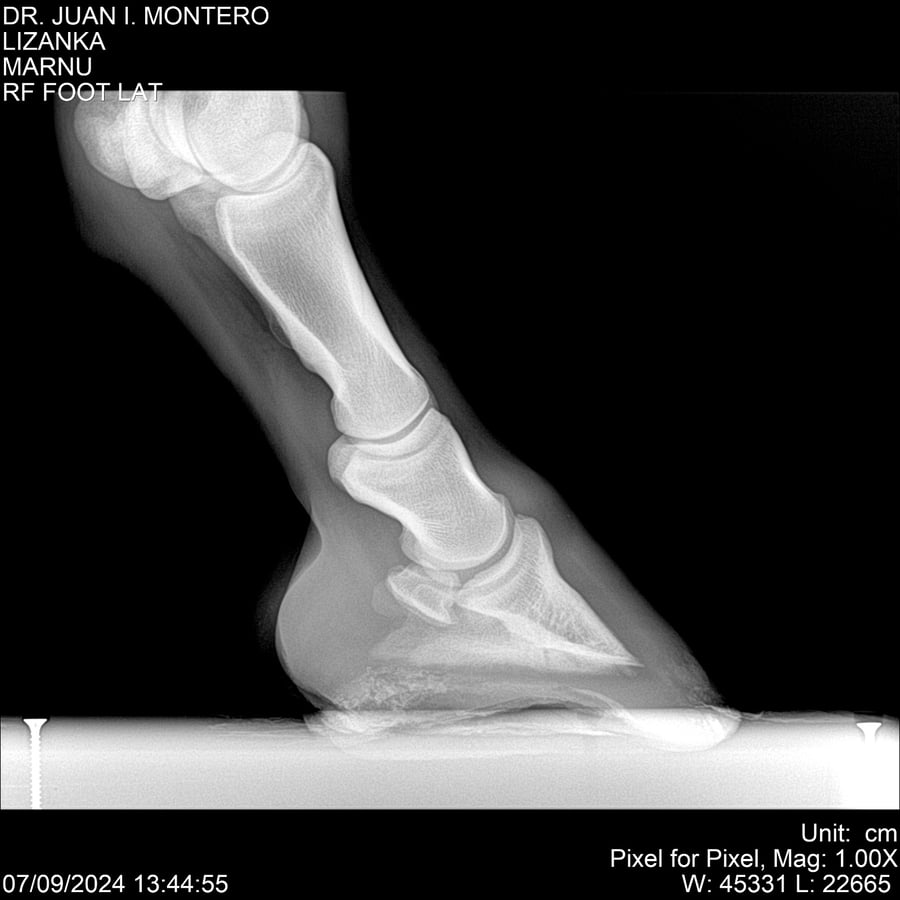

LOTE 18, LIZANKA Lote Anterior Volver al remate Lote Siguiente Ficha Contacto Montevideo - Ficha del Lote Identificador: #282512 Categoría: Yeguarizos Montevideo - 62 Visualizaciones ClicData Contacto Empresa: Abelenda N. R., Walter Hugo Nombre*: Teléfono* : E-mail* : Mensaje Enviar Registrese gratis Este contenido Exclusivo está disponible sólo para usuarios registrados Ingresar